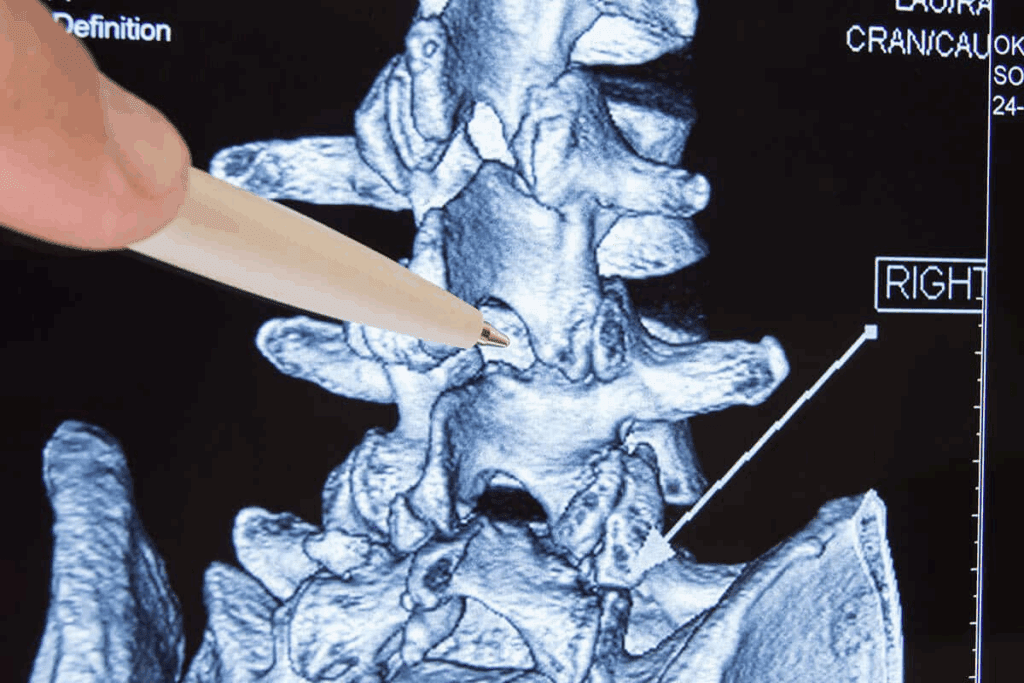

Types of Injections for Spinal Stenosis

There are several types of epidural injections for spinal stenosis. Each targets different areas of the spine. These injections deliver corticosteroids or other medications to the affected area. They help relieve pain and inflammation.

Transforaminal Epidural Injections

Transforaminal injections go through the foramen, the openings where nerves exit. This method targets specific nerve roots.

They’re great for radicular pain from spinal stenosis. They deliver medication directly to the affected nerve, providing relief.

Choosing the Right Injection Approach

The right epidural injection depends on several factors. These include the stenosis’s location and severity, the patient’s health, and their medical history.